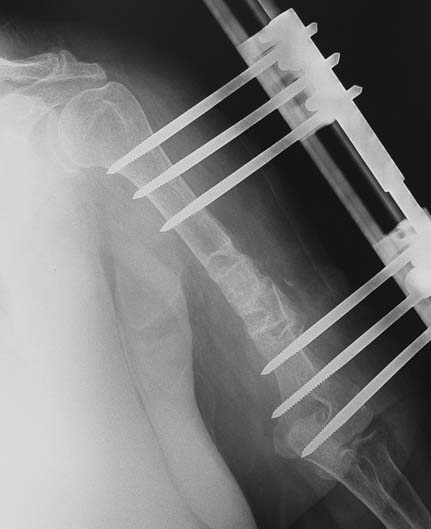

Vaka 3